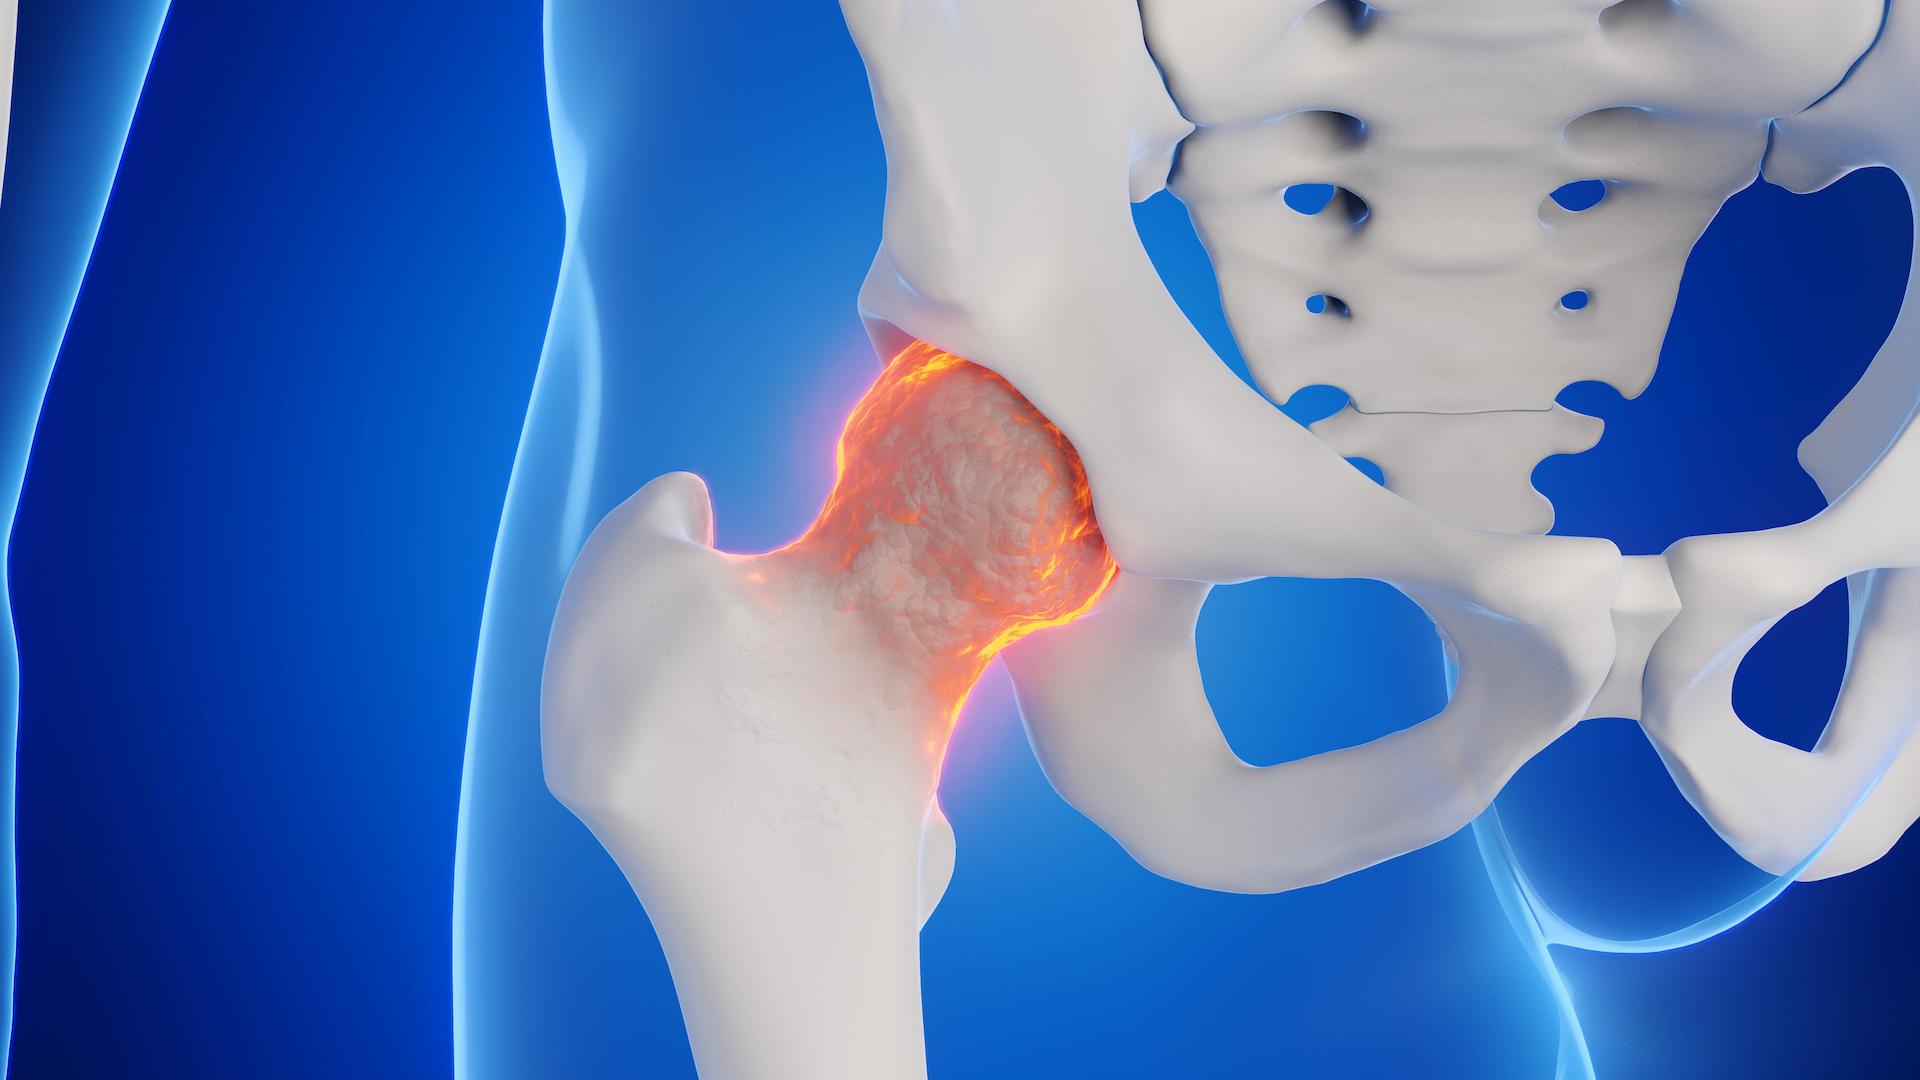

大腿骨頭壊死ってどんな病気?

大腿骨頭壊死とは、大腿骨の先端にあるボールの形をした「大腿骨骨頭」が、血流が途絶えることにより壊死することです。血が通わなくなると骨の修復能力も失うため、一部の骨組織が死んだ状態ですが、基本的に壊死部位が拡大することはありません。

骨の壊死が生じても、壊死の範囲が小さい場合には痛みを生じないこともあります。壊死の範囲が大きかったり、発症部位が悪かったりすると、壊死した部分が次第に圧潰して、強い痛みを伴います。このような状態を「大腿骨頭壊死症」と呼びます。

壊死した部分がつぶれると、つぶれた部分から出血やむくみが起こり、強い痛みを伴います。初期症状では、歩行時や階段昇降時に、股関節に軽度の痛みや違和感を覚える程度ですが、進行すると体重負荷がかかる運動時はもちろん、安静時にも痛みが持続します。